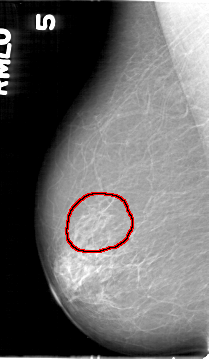

D_4136_1.RIGHT_CC

RIGHT_CC LINES 5251 PIXELS_PER_LINE 2971 BITS_PER_PIXEL 12 RESOLUTION 43.5 OVERLAY

FILE: D_4136_1.RIGHT_CC.OVERLAY

TOTAL_ABNORMALITIES 1

ABNORMALITY 1

LESION_TYPE CALCIFICATION TYPE FINE_LINEAR_BRANCHING DISTRIBUTION SEGMENTAL

ASSESSMENT 4

SUBTLETY 3

PATHOLOGY MALIGNANT

TOTAL_OUTLINES 1

BOUNDARY